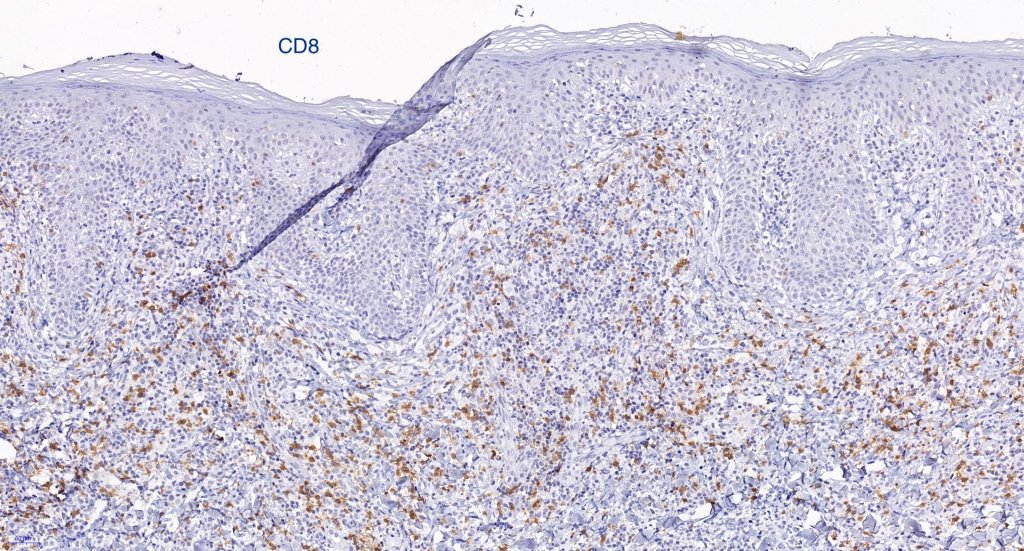

Immunohistochemistry

•Much less often CD8+ve